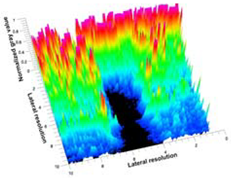

3.3. B-Mode Images

3.5. Echogenicity

4.1. Ultrasonography and Aerogel Dimensional Analyis

| Aerogel Type | US Image | Normalized Intensity Map | 3D Intensity Map | |

|---|---|---|---|---|

| 1 | Muscle |  |  |  |

| 2 | X-silica |  |  |  |

| 3 | X-silica-La2O2S:Eu |  |  |  |

| 4 | SMPU-Mix-14 |  |  |  |

| 5 | SMPU-Mix-18 |  |  |  |

| 6 | BRF-CA |  |  |  |

| 7 | ARF-CA |  |  |  |

| 8 | X-Ca-Alg-2 |  |  |  |

| 9 | X-Ca-Alg-1 |  |  |  |